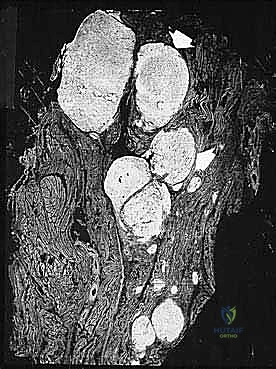

* الساركوما الشحمية (Liposarcoma).

2. ساركوما الأنسجة الرخوة (Soft Tissue Sarcomas)

تنشأ في الأنسجة الداعمة المحيطة بالعظام. تشمل: